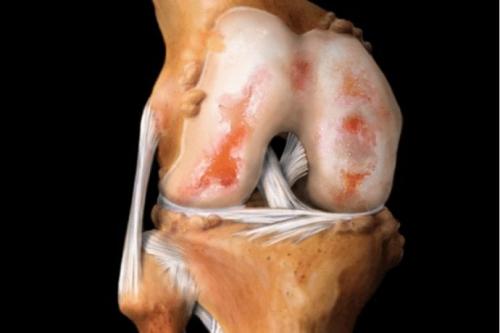

Вид на поражённую хрящевую поверхность.

Ни один из существующих препаратов для восстановления суставов не в состоянии. Некоторые из них замедляют дегенеративные процессы, облегчают самочувствие больного, но не спасают от патологии.

Проблема восстановления хрящей актуальна для более чем 80% людей старше 65 лет, страдающих от деформирующего остеоартроза. Пока не изобретено универсальное средство, возобновляющее структуру хрящей и полностью излечивающее патологию. Однако есть препараты для восстановления хрящевой ткани суставов, обладающие хондропротекторным и регенерирующим действием.

Ни один из существующих препаратов для восстановления суставов не в состоянии вылечить остеоартроз. Некоторые из них замедляют дегенеративные процессы, облегчают самочувствие больного, но не спасают от патологии.